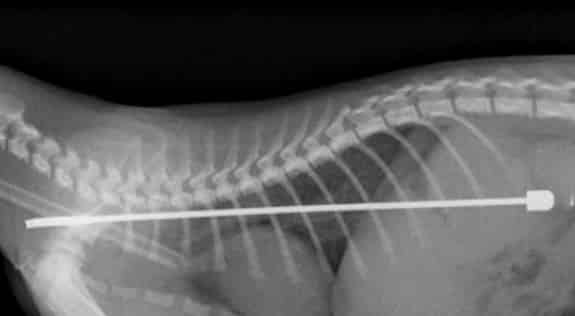

Inglaterra – Um gato precisou ser operado depois que engoliu uma antena de TV de 15 cm, em Parson Cross, na Inglaterra. “Alphie”, o felino da britânica Vanessa Waite, passa bem agora.

A dona se assustou ao ver o raio-X: “Eu não conseguia acreditar quando vi o raio-X. Uma antena enorme em seu corpo minúsculo”. Vanessa levou o animal ao veterinário depois que ele adoeceu.